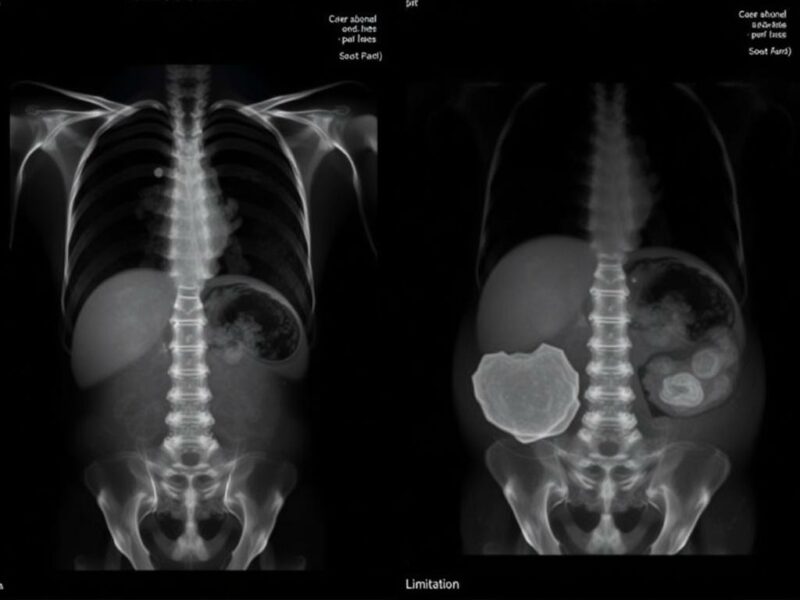

Imagine un paciente de 55 años con dolor abdominal progresivo y vómitos. La radiografía de abdomen muestra niveles hidroaéreos que podrían sugerir obstrucción, pero no explica la causa: una torsión de asas, una hernia incarcerada o una masa compresiva retroperitoneal no son discernibles. En otro caso, una mujer joven con dolor epigástrico y elevación de amilasas puede tener una radiografía normal mientras la TC evidencia pancreatitis aguda con necrosis incipiente. Estos ejemplos muestran la brecha entre lo que la placa puede sugerir y lo que realmente sucede en el abdomen.

- Tomografía computarizada (TC): superior en detección de obstrucción, causa de la obstrucción, inflamación (apendicitis, diverticulitis), colecciones, pancreatitis grave y lesiones retroperitoneales. Es la técnica de elección en la mayoría de los escenarios de dolor abdominal agudo grave o en pacientes de edad avanzada con sospecha de patología intraabdominal compleja.

- Niños: la radiografía puede ser útil para cuerpos extraños, pero la interpretación exige cuidado. La ecografía a menudo aporta más información en abdomen agudo pediátrico y evita radiación.